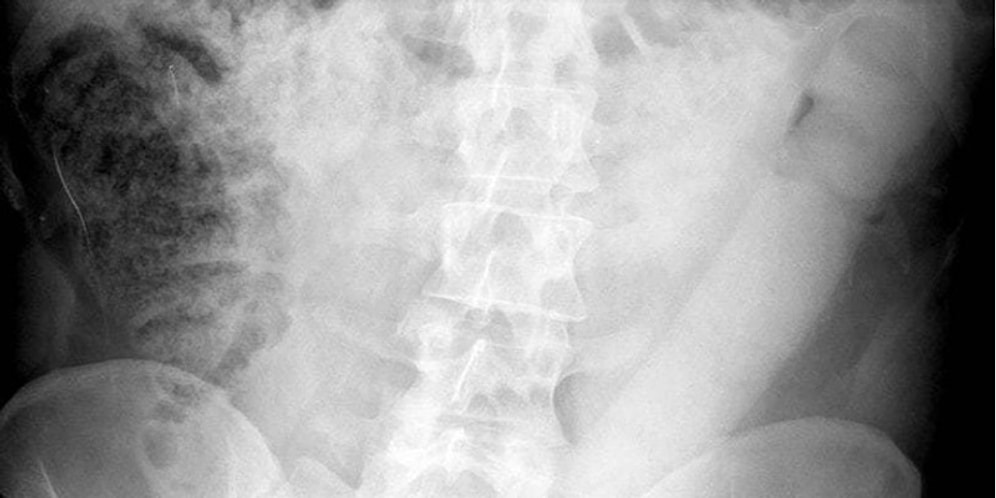

Tıp uzmanları, insanların rektumlarından büyük nesneler çıkarmakta oldukça beceriklidirler. Düzinelerce vaka ve binlerce idare birimi dosyası, insanların vücutlarına nesne yerleştirmede sınır tanımadıklarını kanıtlıyor. Durumu düzeltmek ise acil servis elemanlarına ve sindirim sistemi uzmanlarına kalıyor. Zaman geçtikçe bu konuda ortaya çıkan vakaların sayısı arttığı için çıkarma işlemi için uygulanan teknikler de gelişmiş.İtalyan doktorların bu konuda yeni bir teknik bulmalarını sağlayan, vücudundaki upuzun yapay penis ile hastaneye gelen adama uygulanan cisim çıkarma işlemini IFLscience'dan sizler için derledik.